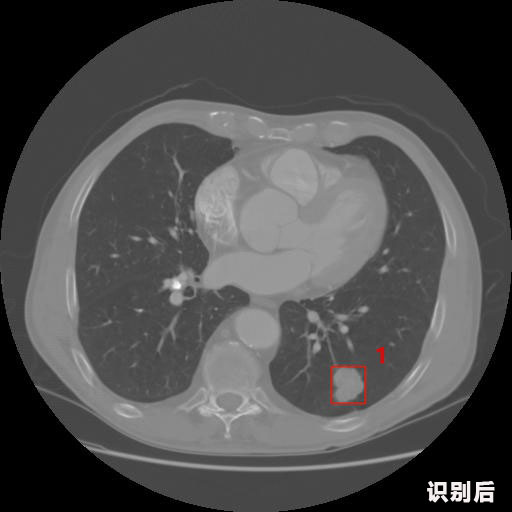

英特健康A(chǔ)I深度學(xué)習(xí)醫(yī)療圖像識(shí)別系統(tǒng)案例_胸部CT

04.jpg

報(bào)告:

1.發(fā)現(xiàn)肺結(jié)節(jié)的可能性為95.56%---位于框指數(shù)位置:[331.70554 366.13406 365.21707 403.96234]